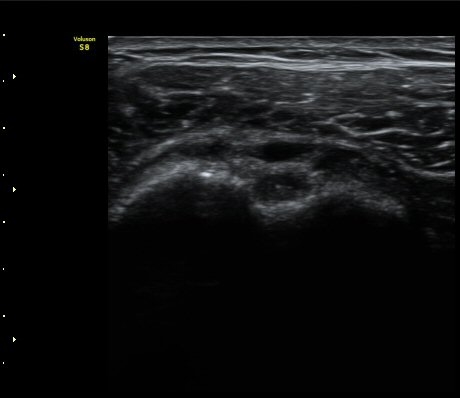

ÃÊÀ½ÆÄ °Ë»ç

2049205267_d18eca99_IMG_20140331_2_1-c.jpg